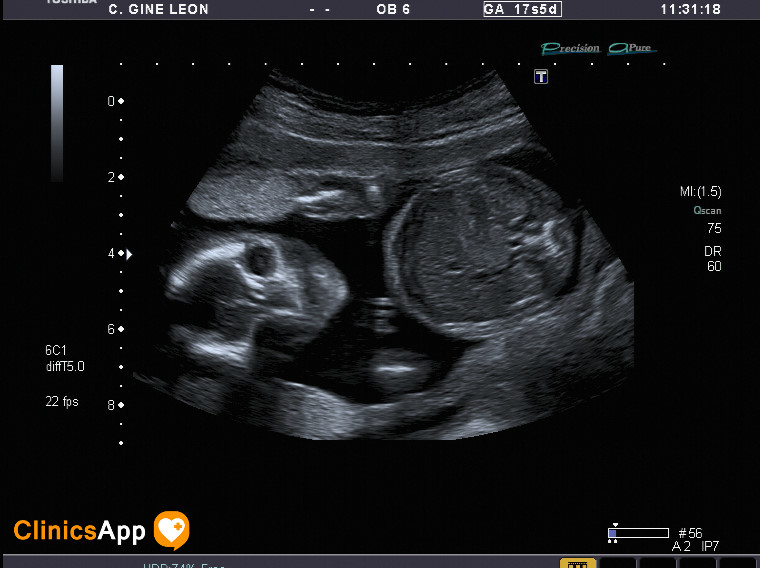

Tercera ecografía (parece que es un niño) Aquí tenemos las fotos de la ecografía de hoy. Parece ser que es un niño, ya no quedan muchas dudas. Fecha publicación 04/05/2016 Publicada por papá Publicada en Fotos, Galerías, Prenatal, Vídeos Comentarios 0 Entrada anterior: Segunda ecografía (mismo día por la tarde), ¡y con vídeo! Entrada siguiente: Cuarta ecografía ¡en 3D! Deja una respuesta Cancelar la respuestaComentario * Nombre * Correo electrónico * Web Guarda mi nombre, correo electrónico y web en este navegador para la próxima vez que comente. Recibir un correo electrónico con los siguientes comentarios a esta entrada. Δ